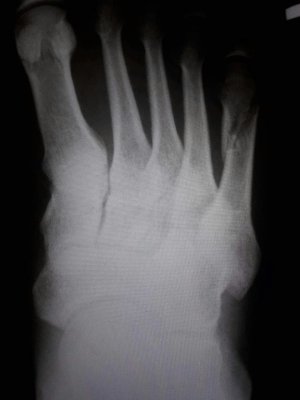

Здравствуйте. Мне 38 лет. Перелом 5-ой плюсневой.

Приложенные снимки - на следующий день после случившегося. Сразу в гипс на 5 недель. Ни в травмпункте, ни в поликлинике лечащий врач даже на упоминали операцию.

Только в травмпункте доктор сказал "... с незначительным смещением, поэтому просто гипс на месяц."

Посмотреть вложение 13116 Посмотреть вложение 13117